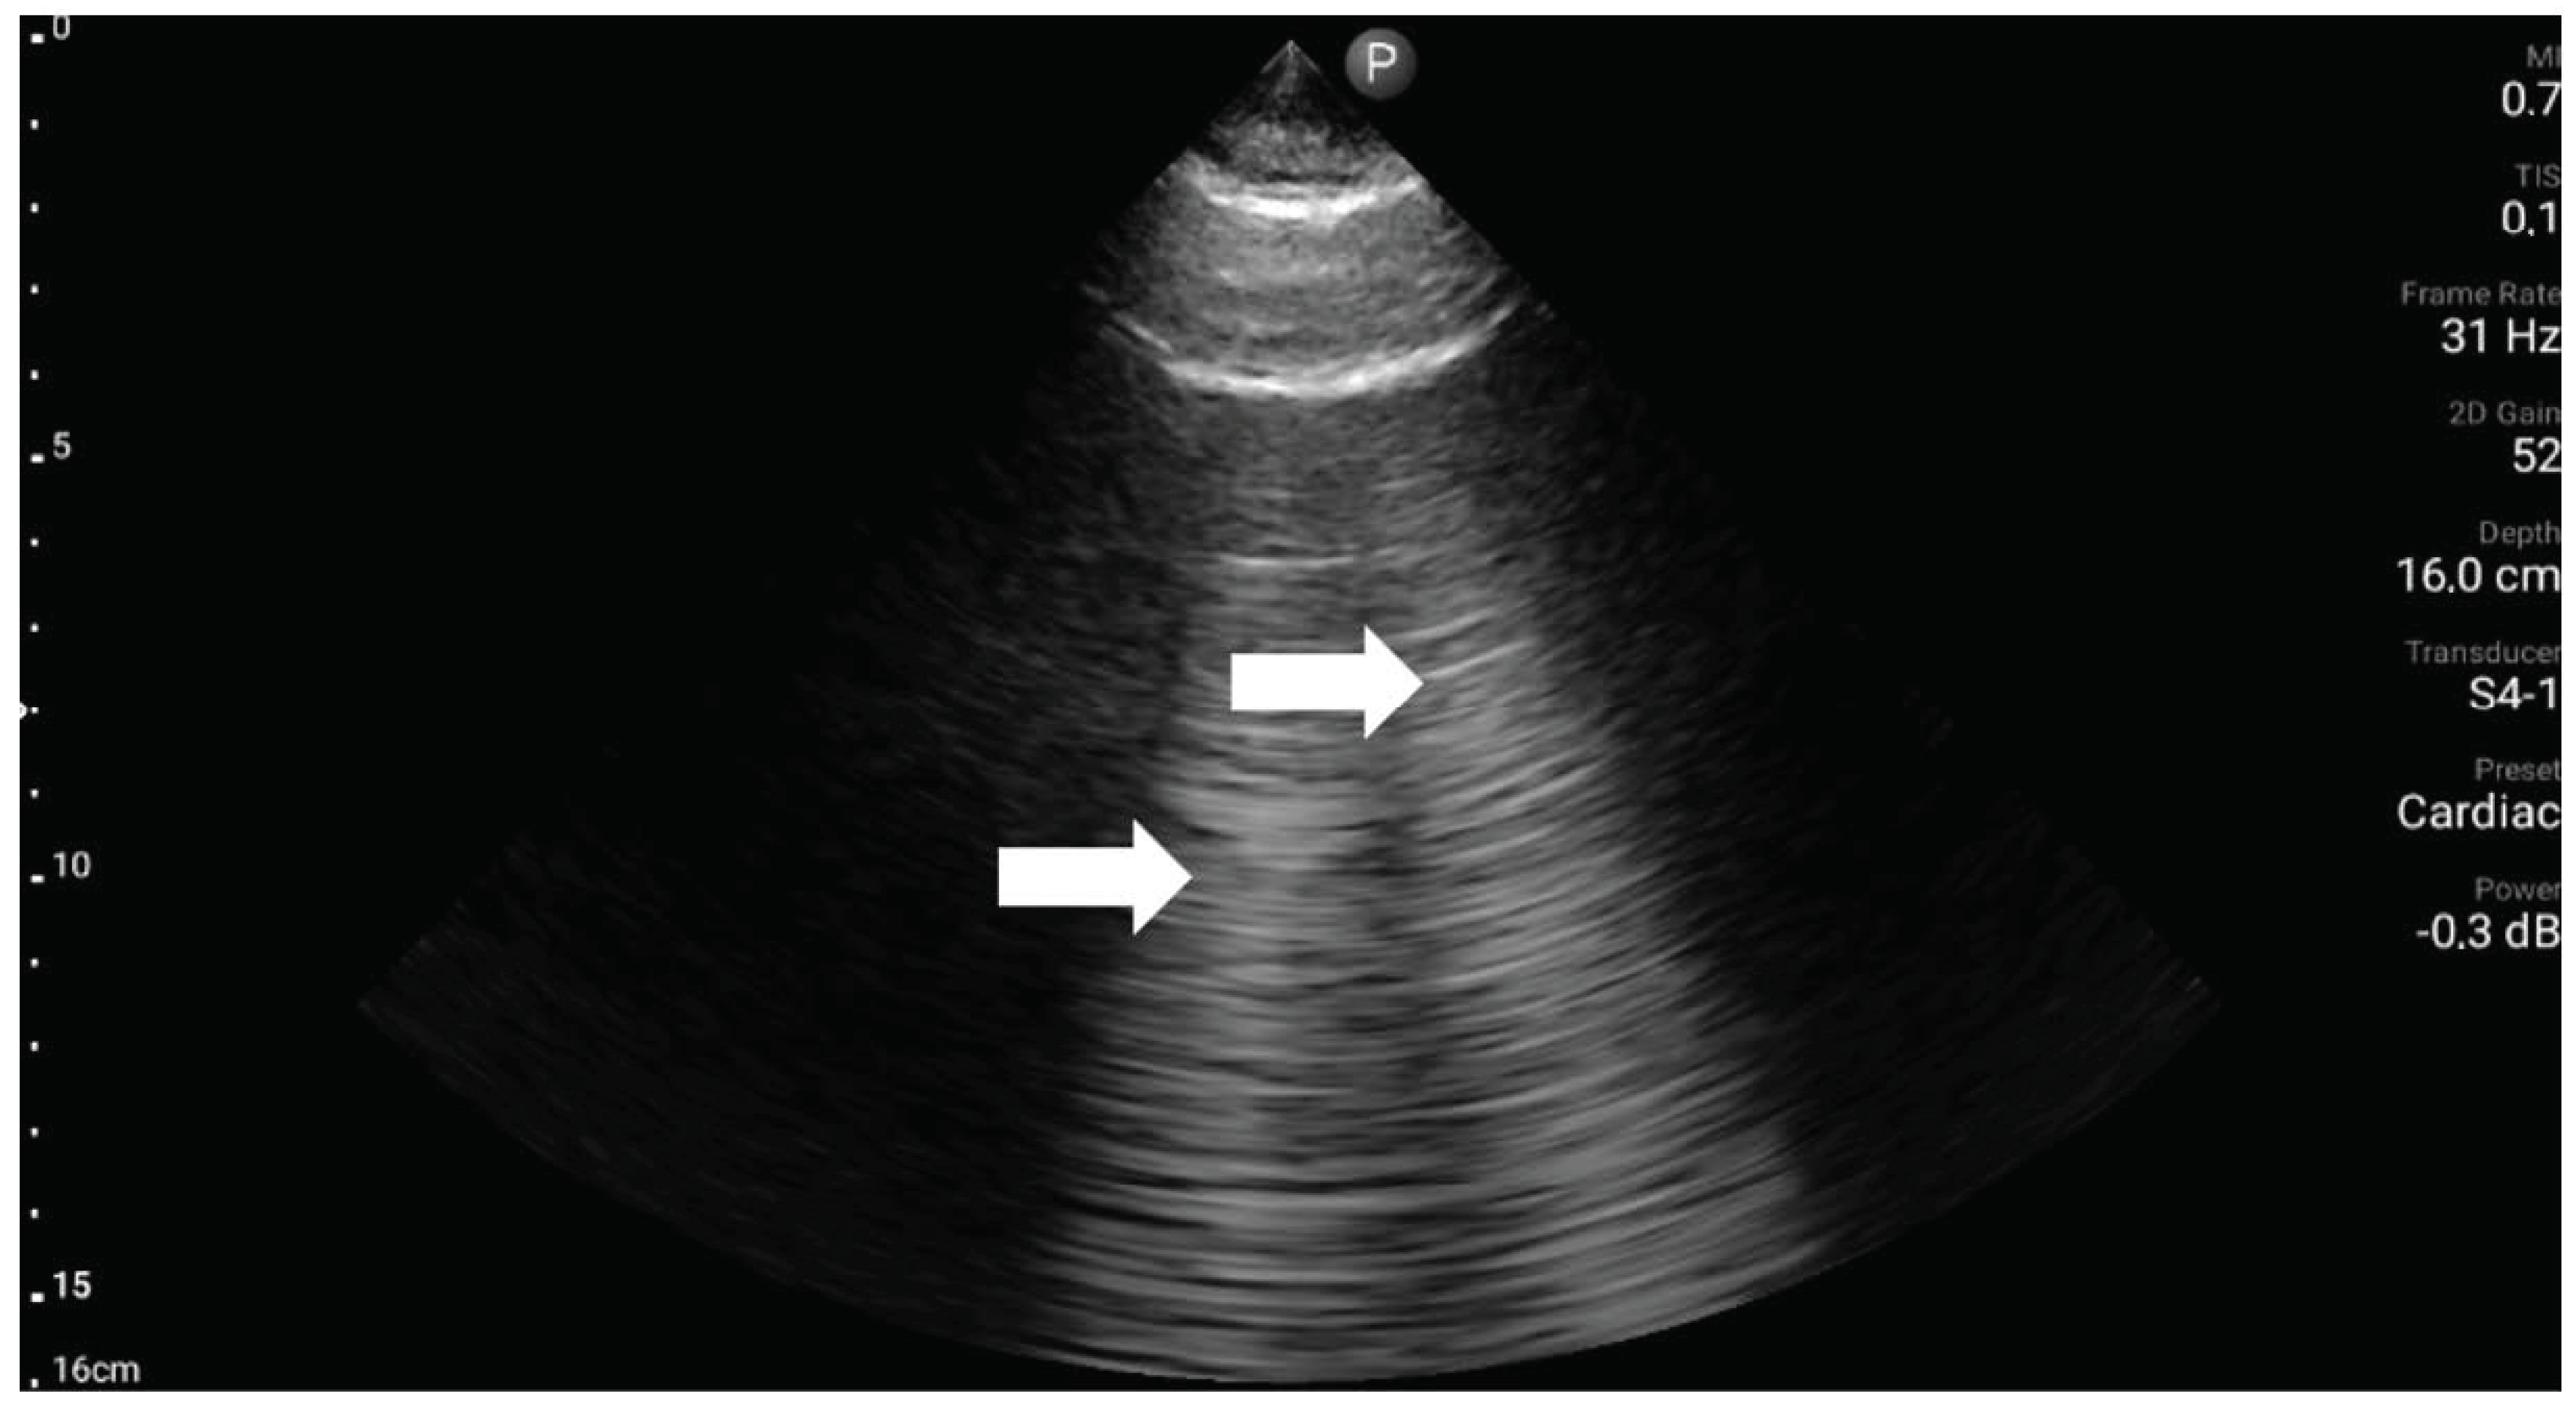

5. BLUE Protocol

To quickly identify and treat the cause of acute respiratory failure, in 2008, Lichtenstein introduced the BLUE (bedside lung ultrasound in emergency) protocol [18]. To date, it is the best known and most accurate of the existing LUS protocols. This study aimed to target diagnostic imaging to identify life-threatening conditions that can lead to acute respiratory failure. Lichtenstein’s task was to develop a protocol by which an ultrasound technician could perform a bedside ultrasound examination in a matter of minutes and implement the correct treatment based on six ultrasound probe positions. The examination is carried out in the chest’s upper (Figure 3), lateral, and posterolateral areas (Figure 4). Within the described six regions on both sides of the chest, the presence of characteristic ultrasound images and signs are assessed, among which are: the A (Figure 5) and B lines (Figure 6), lung sliding sign, lung point (Figure 7), tissue-like sign, and shred sign [18].

It is noteworthy that the previously cited study by Lichtenstein and Mezière [19] did not include a myocardial ultrasound assessment. Given that this is a significant causal group, there is justification for extending the BLUE protocol in this context. A straightforward tool for such assessment is the basic focus assessed transthoracic echocardiography (FATE) protocol. This protocol is based on traditional echocardiography but focused on identifying underlying abnormalities, including evaluation of the size of individual heart cavities, global systolic function, the presence of pericardial sac fluid, cardiac wall hypertrophy, or determination of the degree of inferior vena cava respiratory collapse [21,22].

The FATE protocol, using elements of echocardiography reduced to a simple ultrasound examination of a few minutes, aims at basic identification of the causes of hemodynamic abnormalities [23], which can have a tangible impact on the diagnosis of the causes of dyspnea. The entire examination according to the FATE protocol can often be found in the form of so-called “FATE Cards,” which are schematic protocols indicating how the projections are obtained and the pattern of significant pathologies.

Typical acoustic windows used for this type of study are the right parasternal, subcostal, apical, and left parasternal windows (Figure 8).

Figure 8. Acoustic windows are used during diagnosis according to the FATE protocol, i.e., subcostal, parasternal window in the short and long axis, and apical window (source: author’s material-DK).